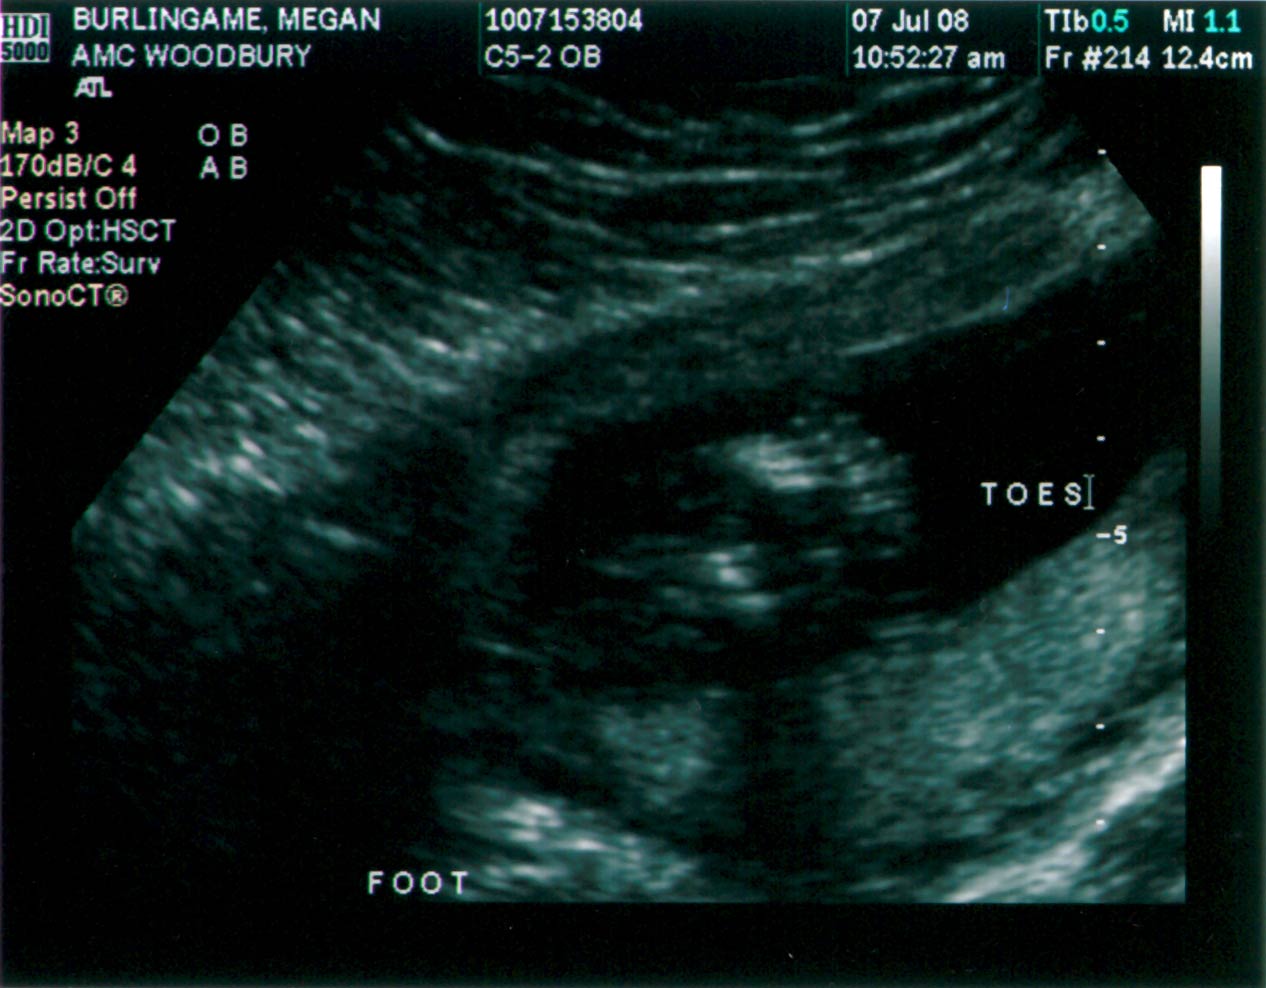

BOY!!! The B’s now have a boy to go with my brother’s girl. The ultrasound went well; the baby looked good. According to the ultrasound measurements, the computer calculated a new due date of November 12. I’m not sure if one date is more accurate than other (11/20 was the initial due date), or if it’s more of a ballpark type of thing. Either way, it’s going to be very close to hunting season (Nov. 8-16). Below are a couple of the ultrasound pics. Click the images for high-res versions.